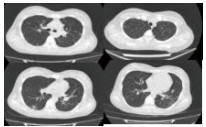

入院后给予抗感染、液体复苏、保肝、补充白蛋白、提升白细胞、输注血小板等对症支持治疗,生命体征逐渐稳定,但患者胸片以及胸部CT仍提示呈进展状态,双肺弥漫性渗出较前明显,肺组织出现“空洞”,并呈进行性破坏,见图 2~3。体温持续波动在38~40℃。入院第8天胸CT提示双侧胸腔积液, 入院第21天胸CT提示双肺渗出及大小不一的“空洞”, 出院时胸部CT,左侧肺气囊样变(图 4)。

| 图 2 入院第8天胸部CT |

| 图 3 入院第21天胸部CT |

| 图 4 出院时胸部CT |

MSSA的影像学特点是在疾病早期,CT改变不明显,仅有小片状肺部浸润,但是,病变发展极快,出现大叶性炎症改变或肺段性浸润,以双下肺野多见。随后病灶内或其周围出现空腔或蜂窝状透亮区,并可发展为肺脓肿。肺浸润、肺脓肿、肺气囊肿和脓胸或脓气胸为金黄色葡萄球菌肺炎的四大影像征象,不同病期以不同的组合表现。肺气囊肿为金黄色葡萄球菌肺炎的典型影像学表现,是支气管周围脓肿使终末细支气管和肺泡发生坏死,当与支气管相通后坏死物质排空形成的直径1~2.5 cm、壁厚1~2 mm、圆形或类圆形薄壁空腔,多发者似蜂窝肺。当临床表现已明显缓解时肺气囊肿仍可存在数月,最后可自然痊愈。

这例患者的疾病过程以及胸部CT表现符合上述改变,“毁损的肺组织”是肺气囊肿,后期随着病情的好转,肺组织基本恢复正常。